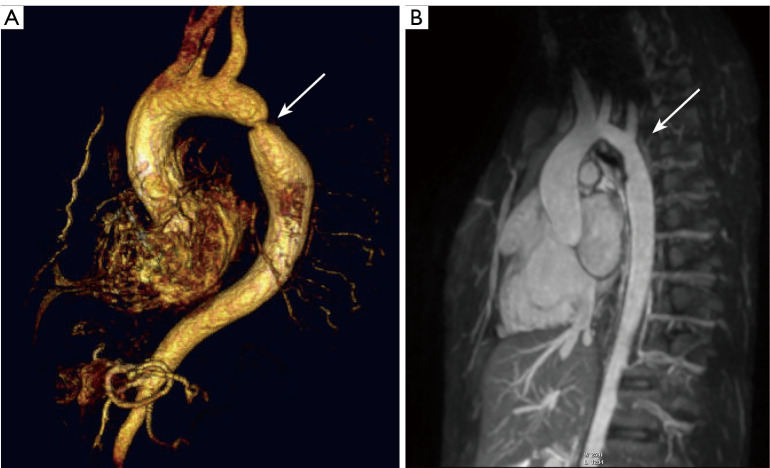

Background: Aortic coarctation (CoA) necessitates long-term monitoring to identify late complications, including re-stenosis, aneurysms, arrhythmias and heart failure. Nonetheless, there remain gaps in understanding the effects of adverse left-ventricular (LV) remodeling at the myocardial tissue level, which may contribute to incipient heart failure. The aim of this study is to evaluate myocardial tissue characteristics in patients with CoA using advanced cardiac magnetic resonance (CMR) imaging techniques to identify markers of adverse tissue remodeling and their association with disease severity, bicuspid aortic valve (BAV), and clinical management strategies such as blood pressure (BP) medication.

Methods: CMR imaging at 3 Tesla was used to determine the myocardial extracellular volume fraction (ECV), native T1, and intracellular water lifetime (τic) by pre- and post-gadolinium contrast T1 mapping in 46 patients (21 male; mean age 20 years) with CoA and 14 age-matched controls. LV volumes, mass, and ejection fraction were obtained from cine CMR. CoA was classified as low grade ["LG" = the maximum flow velocity (Vmax) ≤3 m/s and no re-stenosis, nor arterial hypertension or medication], severe CoA ("sCoA" = Vmax >3 m/s or one of LG's other variables applies), and "CoA with BAV".